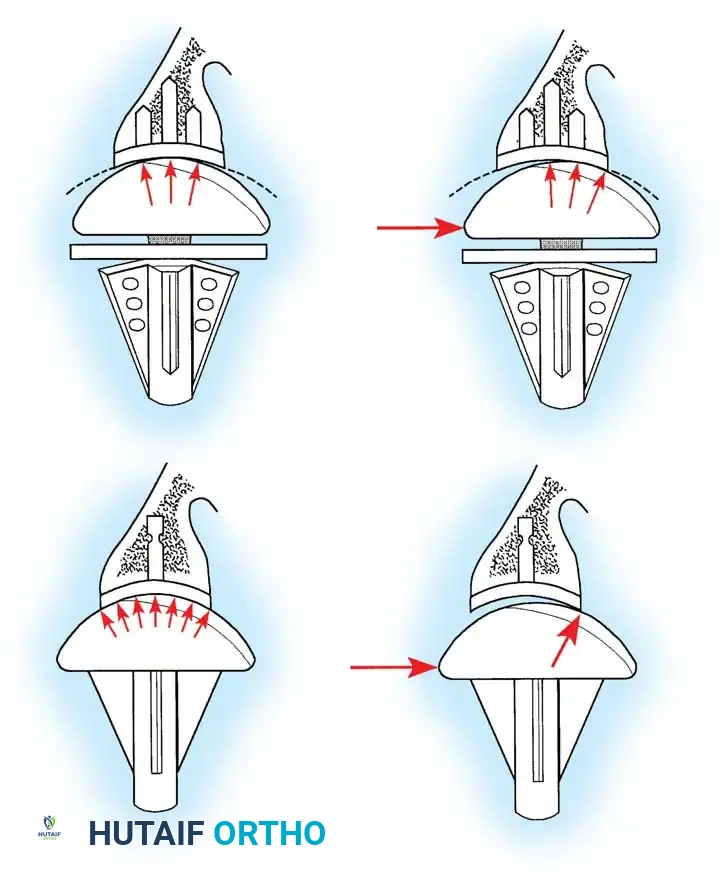

Reverse Total Shoulder Arthroplasty (rTSA)

The rTSA fundamentally alters shoulder biomechanics. By medializing and distalizing the center of rotation, it increases the deltoid moment arm and recruits more anterior and posterior deltoid fibers for elevation, bypassing the need for a functional rotator cuff.

Surgical Nuances for rTSA:

* Glenoid Baseplate: Must be positioned inferiorly on the glenoid to avoid scapular notching. A slight inferior tilt (10 degrees) is often utilized.

* Glenosphere: Typically 36 mm or 42 mm. Larger spheres increase stability and range of motion but may increase the risk of notching.

* Humeral Stem: Often placed in 0 to 20 degrees of retroversion.

Clinical Pearl: Tensioning is the most critical step in rTSA. The joint should be stable in all planes. If the joint dislocates easily, a thicker polyethylene insert or a larger glenosphere is required. However, over-tensioning can lead to acromial stress fractures or brachial plexopathy.

- Instability: Anterior instability is most commonly due to subscapularis failure. Superior instability occurs in anatomical TSA if the rotator cuff fails postoperatively (the "rocking horse" phenomenon), leading to eccentric superior glenoid wear and loosening.

- Glenoid Loosening: The most common cause of late failure in anatomical TSA.

- Scapular Notching (rTSA): Mechanical impingement of the humeral component against the inferior scapular neck during adduction. Minimized by inferior placement and tilt of the glenosphere.